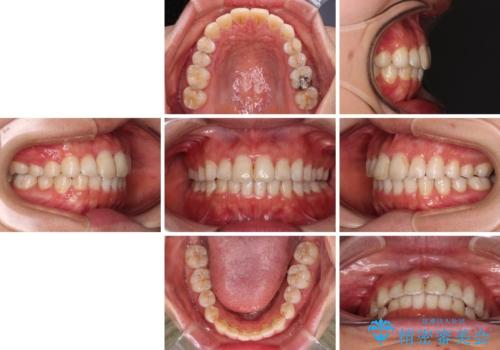

前歯の捻れを改善 インビザラインによる矯正治療

前歯の幅の大きさも気になっていたため、IPRにより叢生を解消するとともに、歯の大きさも改善しました。

- 1年3ヶ月